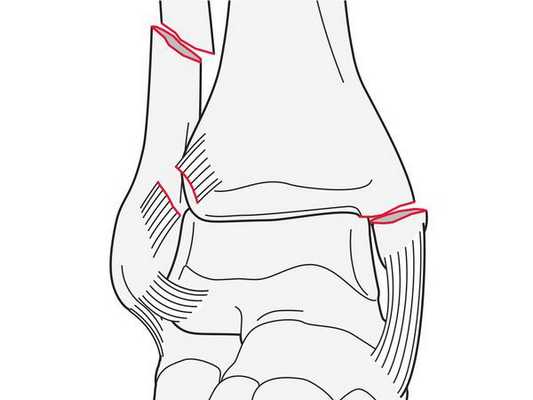

Закрытый оскольчатый перелом внутренней лодыжки правой голени со смещением отломков. Закрытый перелом верхней трети малоберцовой кости правой голени. Повреждение дистального межберцового синдесмоза ( соединения большеберцовой и малоберцовой костей) . Подвывих стопы кнаружи (Maisonneuve-type fracture).

После обследования и уменьшения отёка мягких тканей на четвёртые сутки с момента травмы больному проведено оперативное вмешательство. Под спинномозговой анестезией выполнена открытая репозиция перелома внутренней лодыжки правой голени спицами и стягивающей проволочной петлёй, фиксация дистального межберцового синдесмоза стягивающей петлёй с упорными металлическими площадками.